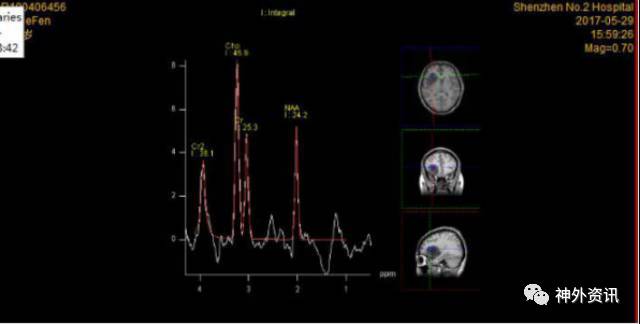

术前波谱